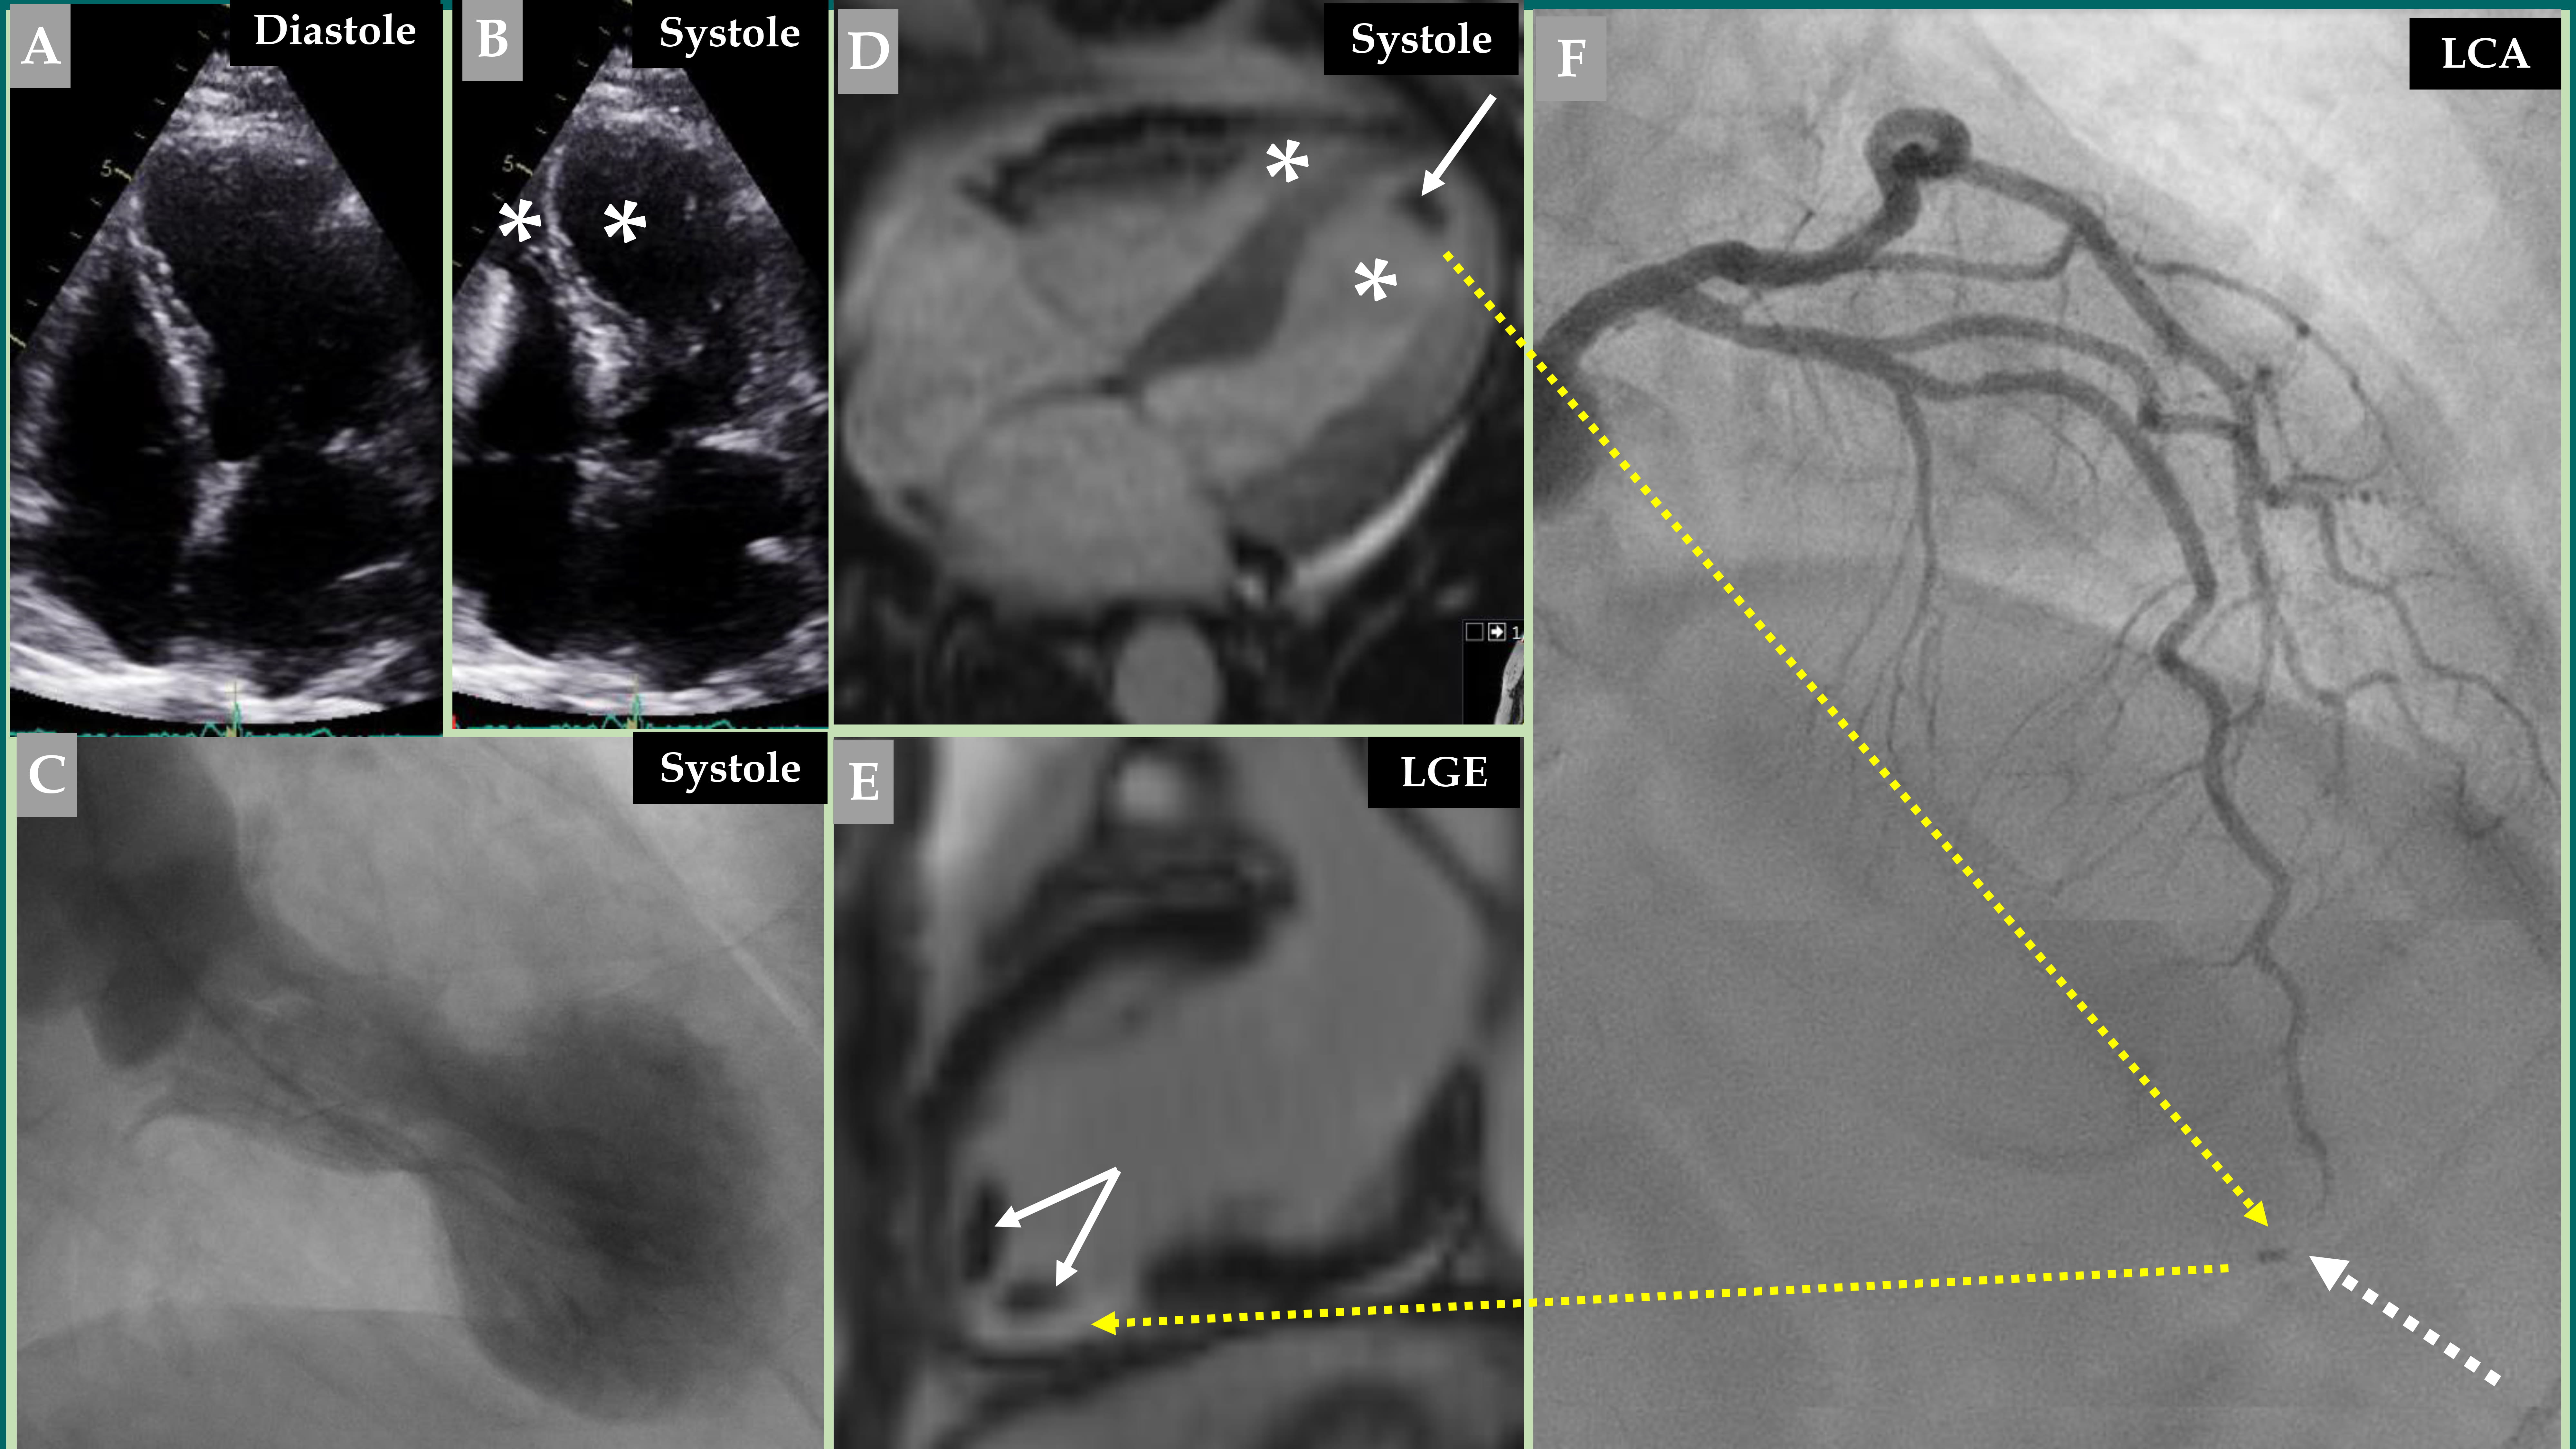

(1) The “to and fro” flow is seen in the proximal segment of the LAD (Fig. 3A,B) at the point where the LAD is located on the hinge point between the normally contracting basal segments in the left ventricle and the akinetic regions in the left ventricle because of increased resistance from the stunned myocardial segments. Slow flow is also observed in the LAD compared to the almost normal flow in the LCx.

(2) In addition to the slow flow in the LAD, systo-diastolic LAD narrowing, which is more pronounced during systole, is observed at the distal two-thirds of the LAD overlying the stunned myocardial segments, which compress the LAD (Fig. 3C).

Fig. 2. Demonstration of an older woman with a mid-apical pattern of TS with complete normalization of the left ventricular function after 5 months. The electrocardiogram (A) shows extensive repolarization changes with certain ST elevations and widespread T-wave inversions. LCA angiography (B) and right coronary artery (RCA) angiography (C) showed no coronary artery occlusion; however, certain other LCA changes are detailed in Fig. 3. Contrast left ventriculography (D, diastole and E, systole) of a mid-apical ballooning pattern of TS. The follow-up contrast left ventriculography 5 months after the index presentation revealed complete normalization of the left ventricular function (F, diastole and G, systole).

Fig. 3. Demonstration of the LCA changes and complications during the acute stage of TS—the same case as presented in Fig. 2. The LCA angiography during diastole (A) and systole (B) is clearly seen, where forward flow in the LAD during diastole (A, yellow arrow) and backward flow in the LAD during systole (B, yellow arrow) due to LAD compression during systole. Signs of slow flow in the LAD are also seen compared to an almost normal flow in the left circumflex artery (LCx) (A and B; LAD, yellow asterisk; LCx, white asterisk). The LAD in the distal two-thirds is thin (C, thin white arrows), which illustrates compression by the myocardial stunning caused by TS in the mid-apical region of the left ventricle. The well-filled three septal branches from the proximal segment in the LAD are clearly seen (C, thicker white arrows) corresponding to the normally contracting basal region in the left ventricle, while the septal branches from the distal two-thirds of the LAD are invisible (C, broken white arrows) due to compression by the myocardial stunning in the mid-apical region of the left ventricle. The mid-apical ballooning pattern of the left ventricle in the acute stage of TS is seen in (D).